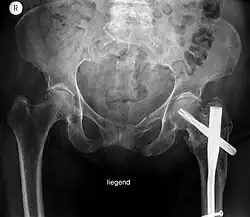

Eine Beckenfraktur ist ein Knochenbruch von Teilen des knöchernen Beckens. Sie tritt meist durch Verkehrsunfälle oder durch Stürze auf. Oft ist das Hüftgelenk beteiligt (Azetabulumfraktur). Innere Blutungen bei Beckenfrakturen sind lebensgefährlich.

Bei der Inspektion und Abtastung ist auf lokale Schwellungen und Verfärbungen, Fehlstellungen, Blockaden im Hüftgelenk, Pulse und Nervenfunktion zu achten. Zum weiteren Ausschluss einer lebensgefährlichen inneren Blutung wird Ultraschall verwendet. Zur Beurteilung der Knochenstruktur werden Röntgen-Übersichtsaufnahmen mit Strahlengang von vorne, evtl. zusätzlich Schrägaufnahmen von 40 Grad oben (in Richtung kaudal = Becken Inlet) oder von 40 bis 60 Grad unten (in Richtung kranial = Becken Outlet) angefertigt. Häufig wird auch direkt ein CT oder ein MRT gefahren. Auch die inneren Organe Harnblase, Vagina und Rektum werden manuell, durch CT- oder MRT-Aufnahme oder nötigenfalls endoskopisch untersucht (seltener).

Instabile Beckenfrakturen müssen meist notfallmäßig durch eine Beckenzwinge oder einen externen Fixateur stabilisiert werden, um eine innere Blutung durch die Kompression zu stoppen. Blutungen verbieten eine Eröffnung des Beckens. Später werden die Brüche operativ durch Platten oder Schrauben fixiert. Mobilisation ist nach etwa zwei Monaten möglich.